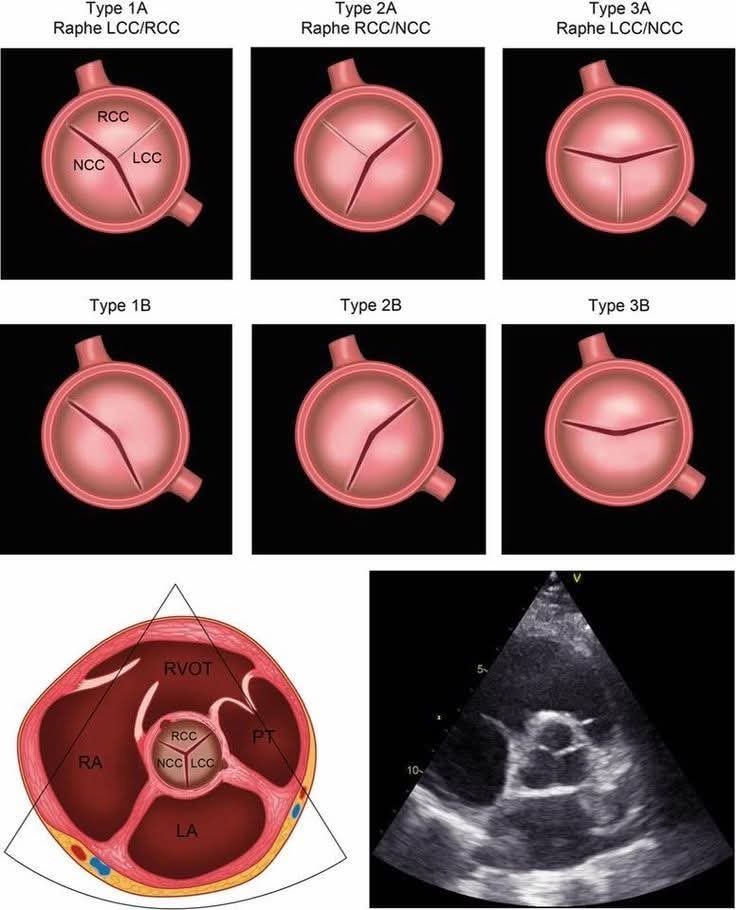

Bicuspid aortic valve (BAV) morphology and its echocardiographic appearance. The valve is categorized based on: ▪︎ Number of raphes (fusion lines) ▪︎ Which cusps are fused. ✅ Type A (one raphe) ● Type 1A (Raphe LCC/RCC) Fusion between Left coronary cusp (LCC) and Right coronary cusp (RCC) → most common. ● Type 2A (Raphe RCC/NCC) Fusion between Right coronary cusp (RCC) and Non-coronary cusp (NCC). ● Type 3A (Raphe LCC/NCC) Fusion between Left coronary cusp (LCC) and Non-coronary cusp (NCC). 👉 These appear as asymmetric bicuspid valves with a visible raphe. ✅ Type 1B / 2B / 3B (no raphe) True bicuspid valves with: ▪︎ No raphe ▪︎ Two symmetric cusps Subtypes depend on orientation of commissures. 👉 Typically more symmetrical (“fish-mouth” opening). 🔹 Key Clinical Pearls: ■ Most common BAV type: LCC–RCC fusion BAV predisposes to: ▪︎ Aortic stenosis. ▪︎ Aortic regurgitation. ▪︎ Ascending aortopathy. ■ Echo hallmark: ▪︎ Systolic doming. ▪︎ Eccentric closure line in diastole. #cardiology #medicine

Ahmed Ata tweet media